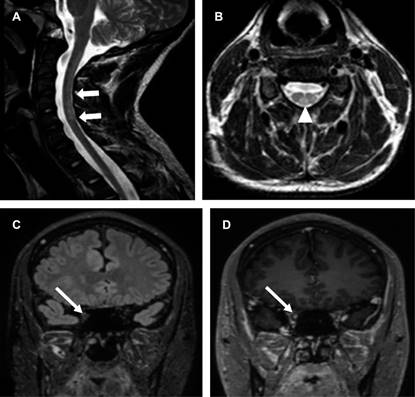

Masculino de 17 años con dos semanas de febrícula, cefalea, ataxia, disminución de agudeza visual de predominio derecho, temblor, fuerza disminuida en extremidades. Laboratoriales: leucocitos 10,100/mm3 con 75%N, proteína C reactiva (PCR) 41.2 mg/L, ELISA VIH negativo, tóxicos en orina negativos. Punción lumbar: leucocitos 70/μL (92% mononucleares), glucosa 68 mg/dL, sugerentes de EMDA, se realizó resonancia de ingreso (Figura 1); se descartó EM por negatividad de bandas oligoclonales IgG específicas, con positividad para anticuerpos anti-MOG mediante EBC. El tratamiento agudo se realizó con metilprednisolona intravenosa a dosis altas con discreta mejoría, en resonancia control presentó compromiso de médula espinal, así como de nervios ópticos (Figura 2); se adicionaron inmunoglobulinas, ocho meses después presentó mejoría sintomática. En resonancia de seguimiento para valoración de tratamiento con disminución de lesiones sin realce de las mismas (Figura 3).

Figura 2: A) Resonancia magnética cervical T2 sagital y B) T2 axial con incremento de la intensidad de señal en la médula espinal (flechas gruesas) y adquisición axial a la altura de disco intervertebral D5-D6 con hiperintensidad que involucra la sustancia blanca evidenciando el signo de la “H axial” (cabeza de flecha). C) Resonancia magnética cerebral coronal FLAIR y D) T1 con gadolinio que muestra la afectación de nervio óptico derecho engrosado, hiperintenso y con realce con medio de contraste (flechas delgadas).